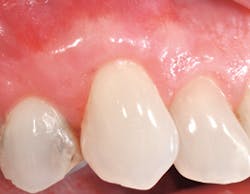

Identification of gingival recession can serve as a perfect example of how the hygienist can make a difference. This condition is a seemingly minor problem that many simply associate with esthetics. However, when patients have gingival recession with bleeding pockets it could be an open source of infection. Patients can have a healthy mouth and practice good oral hygiene and yet, still experience site specific areas of gingival recession. Most are not even aware of it. Areas of recession can be caused by toothbrush abrasion and trauma.3 All too often it is regarded as an unavoidable part of the aging process.

In some patients, areas of recession are stable based on previously documented measurements with no requirement for specific intervention or treatment . But with other patients, we know otherwise. Recession can lead to the exposure of the tooth's root surface, causing esthetic problems and sensitivity. Early diagnosis and treatment of gingival recession is important because the situation can worsen to where predictable root coverage isn't possible and esthetics become compromised. Many hygienists and clinicians see this problem in patients; however, they don't necessarily inform them so they could opt for treatment sooner. Correct initial diagnosis is key.4 The goal is to deliver optimal treatment outcomes and provide our patients with more predictable results.